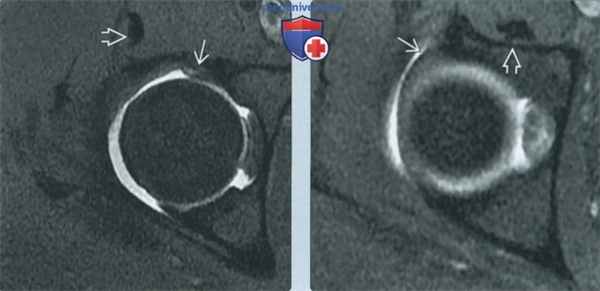

(Слева) МР-артрография в режиме Т1ВИ FS, аксиальный срез: выявляется подвздошно-поясничный импинджмент. В положении «на 3 часа» определяется неровный контур передней суставной губы, в толще которой отмечается контрастный препарат. Сухожилие подвздошно-поясничной мышцы в этом месте перекидывается через суставную губу и располагается спереди от нее.

(Справа) МР-артрография в режиме Т1ВИ FS, аксиальный срез, этот же пациент: в положении «на 1 час» суставная губа выглядит интактной. Подвздошно-поясничная мышца проходит кпереди от вертлужной впадины.

(Слева) МР-артрография в режиме PD FS, сагиттальный срез, этот же пациент: в положении «на 3 часа» визуализируется разрыв суставной губы. Спереди ее пересекает сухожилие подвздошно-поясничной мышцы.

(Справа) МР-артрография в режиме PD FS, сагиттальный срез, этот же пациент: отмечается, что верхняя часть суставной губы интактна. При ее разрыве следовало бы заподозрить скорее бедренно-вертлужный, чем подвздошно-поясничный импинджмент.